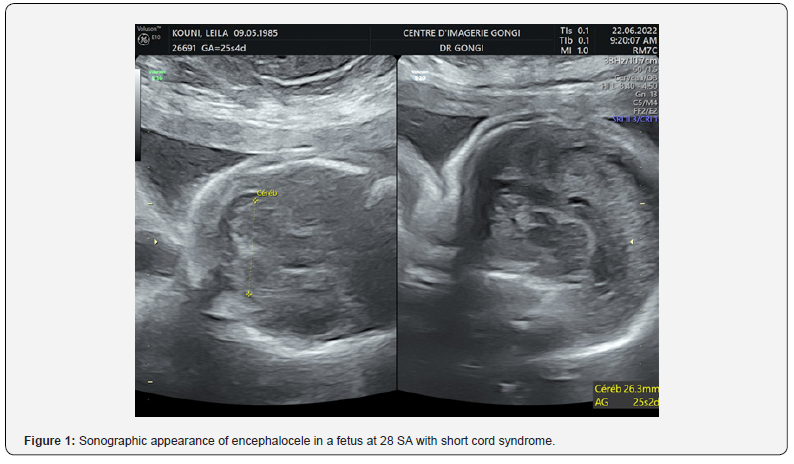

Obstetrical ultrasound revealed an evolving mono-fetal pregnancy, with amitotic fluid in diminished quantity, a cerebral floor without anomalies (Figure 1), a large coelosomycompléte, heart, liver and intestine bathed in amniotic fluid, (Figure 2) without individualization of the diaphragm, with anomalies of the spine (Figure 3) anomalies of the lower limbs, a right clubfoot. The fetus appeared to be attached to the placenta. An umbilical cord containing two arteries and a very short vein (Figure 4), The most likely diagnosis was short cord syndrome. After discussion with the parents and a psychological interview with the woman, the pregnancy was terminated. Macroscopic examination at birth revealed a male fetus weighing 500g, with a marked anterior complete coelosomy (heart, liver and intestine exteriorized). Narrow thorax. The spine is angulated, and the lower limbs are club-footed (Figure 4). The fetus was attached to the placenta by a very short 6 cm cord, with 2 arteries and one vein (Figure 5). The fetus was pathologically examined for other visceral malformations. However, all the ultrasound findings and macroscopic examination (Figure 6) enabled the diagnosis to be accepted.

Cephalic anomalies: exencephaly, anencephaly, encephalocele, facial defects and, in 71% of cases, increased nuchal translucency.